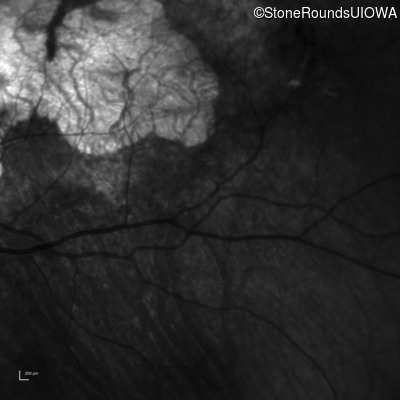

Infrared Fundus Photograph - Right - 20/20 -2 sc

Exemplar